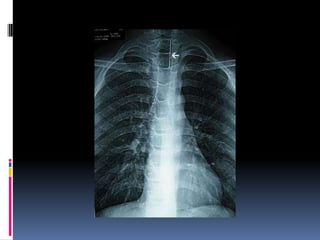

 Estudios Radiológicos.-

 Rx. DeTórax AP. y Oblicuo.

Localización • Inmediatamente pordebajo del músculo cricofaringeo. • Encima de la unión gastroesofágica. • En los relieves que establecen el cayado de la aorta y el bronquio principal izquierdo.

Diagnostico  Estudios Radiológicos.- Rx. Simple de Esófago Cervical vista Lateral.  Fluoroscopía de Esófago con mota de algodón  Embebida en bario.  Rx. DeTórax AP. y Oblicuo.  Exploración Endoscópica.